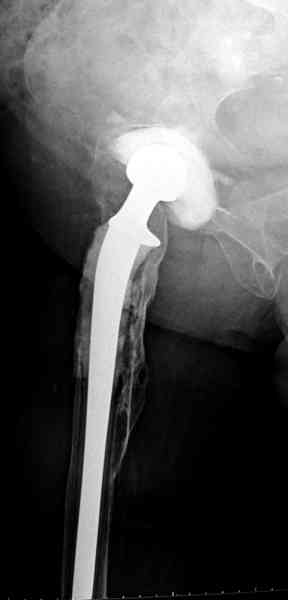

Повторная операция по удалению тотального протеза с irrigation&debridment, канал после очистки цемента обильно промыт и рассверлен римером.

Приготовлен цемент из расчета: Tobramycin 2.4 g (2 флакона), Vancomycin 2 млн (4 флакона) и 2 упаковки цемента с добавлением дополнительного флакона цементной жидкости.

После обработки ацетабулярного компонента, ещё в мягком цементе в полости вертлужной впадины головкой бедренного компонента сделана выемка для головки, чтобы свежий цемент не прилипал к головке. Головку бедренного компонента завернул обычной стерильной фольгой, которую после образования выемки отлепил от головки.

Для спейсера в бедро использовал старый длинный бедренний компонент меньшего диаметра, облепленный со всех сторон цементом с антибиотиком.

Наглухо ушитая рана с дренажом зажила первично, после чего с больной потерял контакт, и только недавно, через 8 лет я осмотрел её. Она без проблем нагружает на конечность и передвигается с помощью трости. От окончательной операции по реконструкции отказывается, довольная результатом.

Имеются литературные данные, когда спейсер держали не более 6 месяцев, но этот случай бьет все рекорды, может быть для наших людей, обременных финансовыми трудностями, нужна другая шкала оценки сроков нахождения спейсеров.

№3-6 снимки с осложнением

и последние снимки.